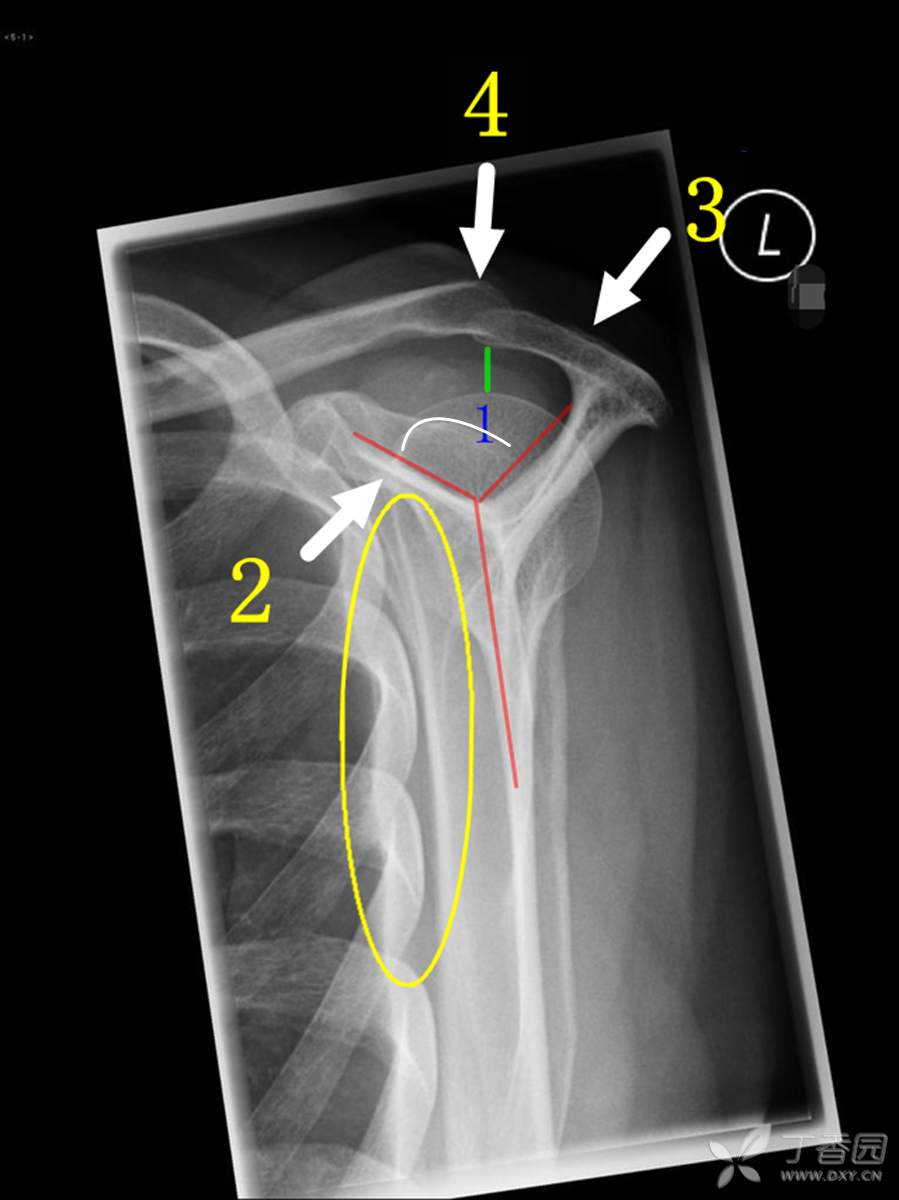

肩峰撞击综合征临床及影像诊断之二 - 丁香园论坛

图片尺寸899x1200